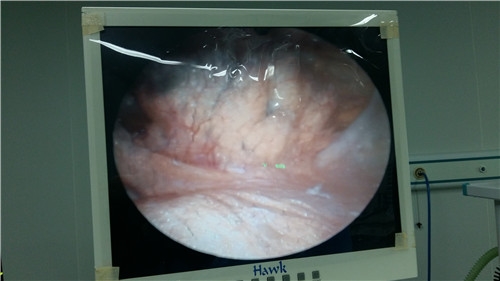

关节镜是一种观察关节内部结构的直径5mm左右的棒状光学器械,是用于医师诊治关节疾患的内窥镜。关节镜在一根细管的端部装有一个透镜,将细管插入关节内部,关节内部的结构便会在监视器上显示出来。因此,可以直接观察到关节内部的结构。>>点击了解关节镜的治疗效果和治疗费用